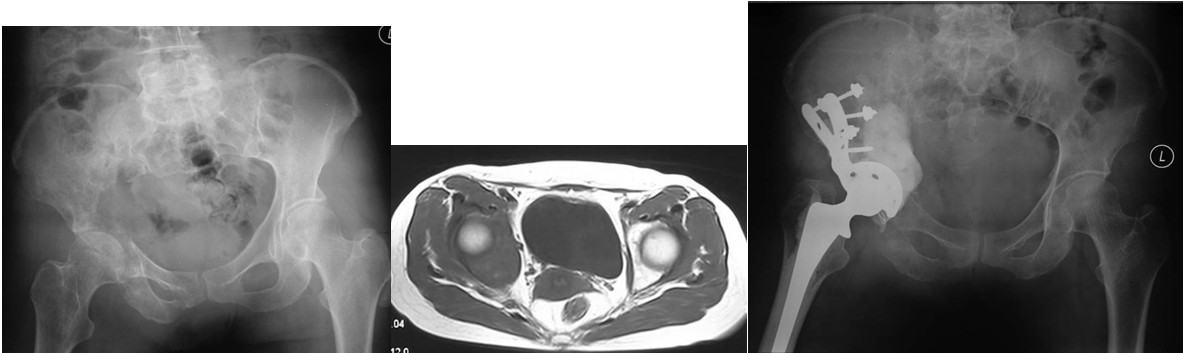

本组病例中不同部位髋臼转移癌的手术方式(图1):I型:髋臼下壁骨破坏、上壁及内、外侧壁完整, 采用肿瘤刮除、普通水泥型全髋置换术。II型:髋臼内、外侧壁破坏,上壁骨质完整, 采用带翼网杯+水泥型全髋置换术。 III型:髋臼上壁及内、外侧壁均破坏,采用肿瘤刮除后、骨水泥填充髋臼上壁骨缺损,带翼网杯+水泥型全髋或组合式人工半骨盆。IV型:孤立性骨盆转移, 以治愈为目的, 采用肿瘤整块切除,组合式人工半盆置换术。

图1, 髋臼转移癌的分型示意图(北京大学人民医院)

图2,女,31岁,乳腺癌髋臼转移, Harrington I型

图3,女,55岁,肺癌髋臼转移, Harrington II型

图4,女,52岁,乳腺癌髋臼转移, Harrington III型

图5,男,69岁,肾癌髋臼转移, Harrington IV型